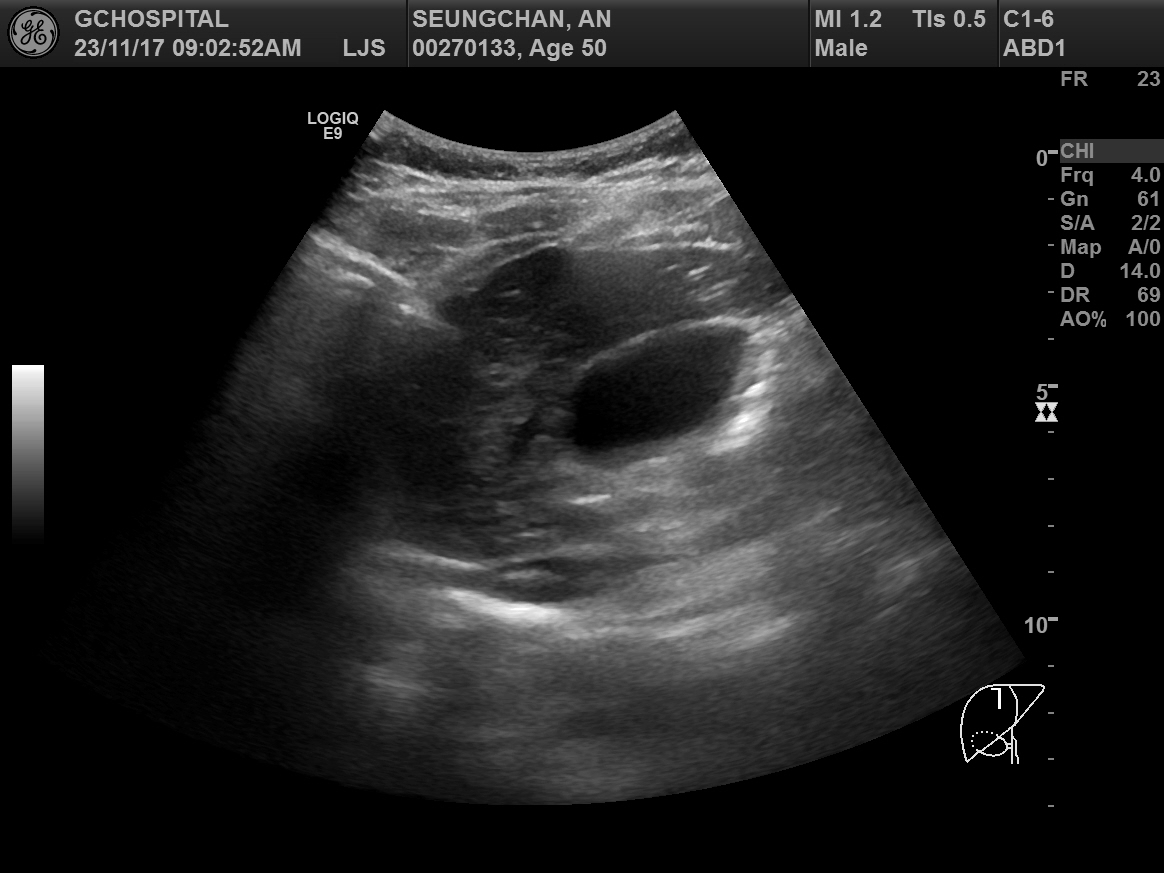

위의 두 영상은 간초음파에서 우간정맥(Rt. hepatic vein)의 장축을 따라 얻은 B모드 및 컬러도플러 영상입니다. 간실질 에코가 매우 거칠고 불균일한 만성 간질환 환자인데, 도플러영상에서 장축 전체에 걸쳐 뚜렷하게 확인할 수 있는 우간정맥이 B모드영상에서는 희미하게 일부분만 보입니다. 심지어 확인되는 부분도 컬러 도플러영상에서 보이는 것보다 훨씬 가늘어보이죠.

반면, 혈류가 반대방향이어서 빨갛게 보이는 간문맥(Rt. portal vein)의 경우는 B모드 영상에서도 간문맥 벽이 뚜렷하게 보일 뿐 아니라, 굵기도 컬러도플러 영상에서 확인되는 것과 별로 큰 차이가 나지 않습니다.

다음으로 중간정맥(middle hepatic vein)의 B모드 및 컬러도플러영상입니다. 컬러도플러영상에서 또렷하게 보이는 중간정맥이 B모드영상에서는 마찬가지로 매우 가늘고 희미하게 보입니다. 컬러도플러 영상에서 보여주는 중간정맥의 굵기가 실제 직경과는 차이가 있겠으나, B모드에서 보이는 것보다는 훨씬 직경이 클 것으로 보이며, B모드영상에서는 전혀 확인할 수 없었던 가지부분들도 컬러도플러영상에서는 또렷하게 확인됩니다.

간초음파를 시행하면서 확인해야 하는 표준영상 중에는 우간정맥의 장축을 포함하는 영상이 포함되어있습니다. 마찬가지로 간좌엽의 시상면영상을 확인할 때에도 좌간정맥(Lt. hepatic vein)이 포함되어 촬영하는 게 보통입니다. 그렇게 간정맥을 확인하는 과정에서 위와 같이 간정맥이 잘 보이지도 않고, 실제 직경보다 훨씬 작게 보이는 이런 현상은 현장에서는 굉장히 흔한 현상입니다.

B모드영상에서 간정맥이 실제보다 훨씬 얇고 희미하게 보이거나, 아예 잘 보이지 않는 이유는 간정맥의 혈관벽이 얇아서 초음파신호가 반사되지 않아 영상에서 혈관벽을 특정할 수 없기 때문입니다. 특히 간실질의 에코음영이 거칠거나 간섬유화가 심하게 진행된 만성 간질환 환자들에서 간정맥을 확인하지 못하거나, 굉장히 가늘게 보이는 경우가 많습니다.

그런 장비의 발전과 진보가 있기 전까지는 간초음파의 표준영상을 얻는 과정에서 간정맥, 특히 우간정맥의 장축을 보여주는 영상을 촬영할 때에는 좀 더 번거롭더라도, 컬러도플러영상을 함께 촬영하면서 우간정맥을 확인하는 것도 좀 더 신뢰할만한 간초음파영상을 얻기 위해 권장될 수 있겠다는 생각입니다.